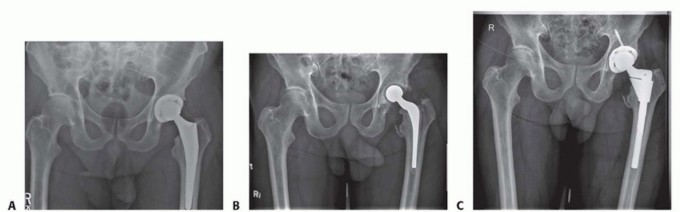

Acetabular Reconstruction:

The acetabulum is sequentially reamed to bleeding host bone. The Paprosky classification guides reconstruction:

* Paprosky Type I and II defects are typically managed with highly porous hemispherical titanium components (jumbo cups) and multiple screws.

* Paprosky Type III defects require the restoration of the hip center utilizing highly porous metal augments (e.g., trabecular metal) to fill superior or medial voids. If column continuity is compromised (pelvic discontinuity), a custom triflange acetabular component or a cup-cage construct is mandated to provide mechanical stability.

Femoral Reconstruction:

Femoral bone loss is similarly addressed based on the Paprosky femoral classification.

* Minimal bone loss allows for the use of standard fully porous-coated cylindrical stems.

* Significant proximal bone loss with an intact diaphysis (Paprosky Type II or IIIA) is optimally managed with a modular fluted tapered titanium stem. These stems achieve diaphyseal fixation through rigid distal engagement, bypassing the proximal deficiency. The modularity allows for independent control of version, offset, and leg length.

* If an ETO was performed in the first stage, the osteotomy fragment is reduced around the new stem and secured with multiple cerclage cables.

The articulation is selected based on patient stability. Given the high risk of dislocation in revision surgery, large diameter femoral heads or dual mobility constructs are heavily favored. The wound is closed in multiple layers over closed suction drains to eliminate dead space and prevent hematoma formation.